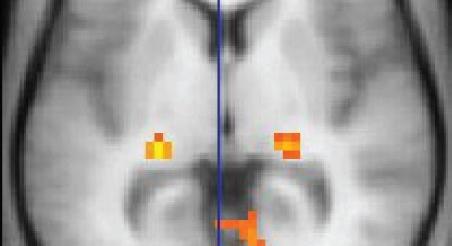

10 éve öltek met 132 fiatalt egy francia szórakozóhelyen – a túlélők agyát MRI-vel vizsgálják